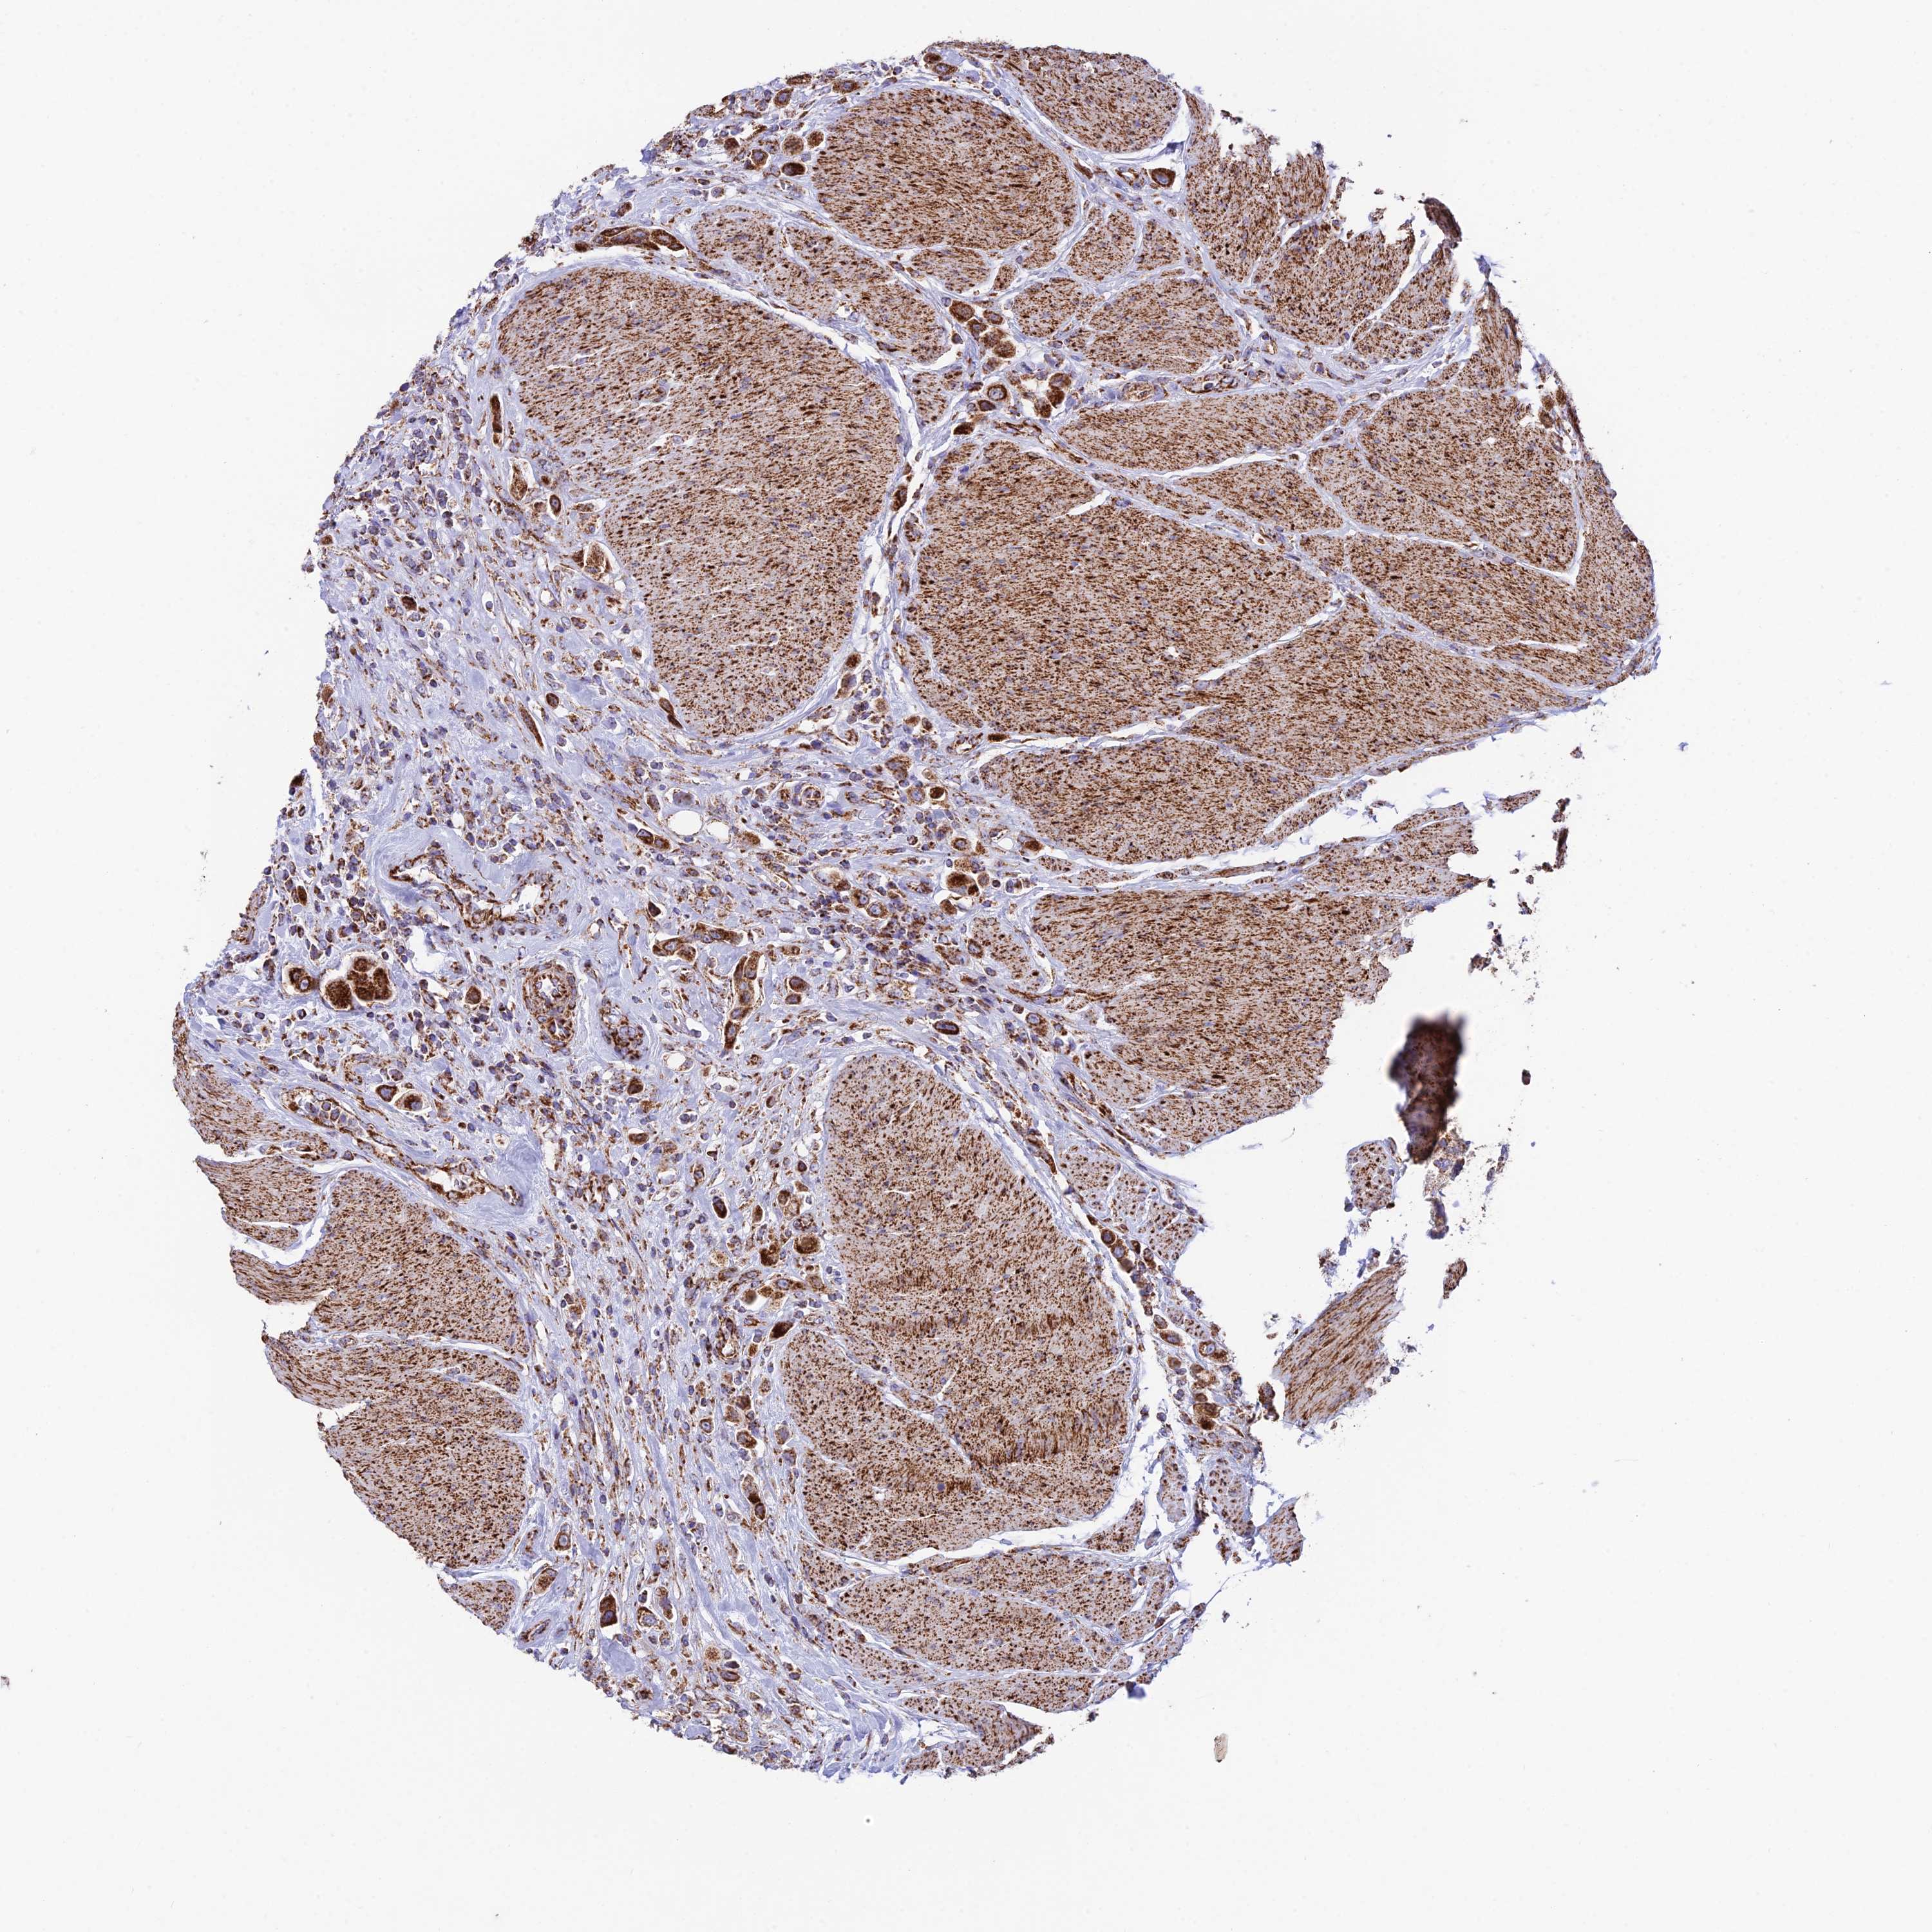

UROTHELIAL CANCER - Protein expressioni

A mouse-over function shows sample information and annotation data. Click on an image to view it in a full screen mode. Samples can be filtered based on level of antibody staining by selecting one or several of the following categories: high, medium, low and not detected. The assay and annotation is described here.

Note that samples used for immunohistochemistry by the Human Protein Atlas do not correspond to samples in the TCGA dataset.

Antibody stainingi

Antibody staining in the annotated cell types in the current human tissue is reported as not detected, low, medium, or high, based on conventional immunohistochemistry profiling in selected tissues. This score is based on the combination of the staining intensity and fraction of stained cells.

Each image is clickable and will lead to virtual microscopy that enables deeper exploration of all samples and also displays staining intensity scores, fraction scores and subcellular localization as well as patient and tissue information for each sample.

Antibody HPA042935

Staining

High

Medium

Low

Not detected

Intensity

Strong

Moderate

Weak

Negative

Quantity

>75%

75%-25%

<25%

None

Location

Urothelial carcinoma, High grade

Urothelial carcinoma, Low grade

Urothelial carcinoma, NOS